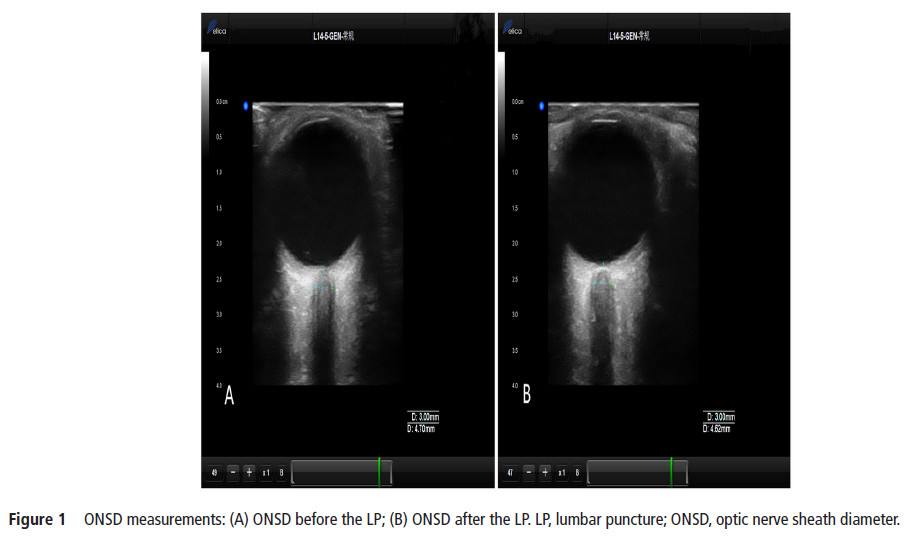

The current study aimed to identify whether ultrasonographic measurements of optic nerve sheath diameter (ONSD) could dynamically and sensitively evaluate real-time intracranial pressure (ICP). ONSD

measurements were performed approximately 5 min prior to and after a lumbar puncture (LP). A total of 84 patients (mean±SD age, 43.5±14.7 years; 41 (49%) men; 18 patients with elevated ICP) were included in the study. The Spearman correlation coefficients between the two observers were 0.779 and 0.703 in the transverse section and 0.751 and 0.788 in the vertical section for the left and right eyes, respectively. The median (IQR) change in ONSD (ΔONSD) and change in ICP (ΔICP) were 0.11 (0.05–0.21) mm and 30 (20–40) mmH2O, respectively, for all participants. With a reduction in cerebrospinal fluid pressure, 80 subjects (95%) showed an immediate drop in ONSD; the median (IQR) decreased from 4.13 (4.02–4.38) mm to 4.02 (3.90–4.23) mm (p<0.001). Significant correlations were found between ONSD and ICP before LPs (r=0.482, p<0.01) and between ΔONSD and ΔICP (r=0.451, p<0.01). Ultrasonic measurement of ONSD can reflect the relative real-time changes in ICP.【The ONSD was measured with the Delica MVU-6300 (Shenzhen, Guangzhou, China),】

【作者注:腰穿前后对比视神经鞘变化,发现超声检测视神经鞘直径可以实时显示颅内压改变,也进一步证实了关于视神经鞘研究的规范操作流程,应该在腰穿之前进行视神经鞘测量】。